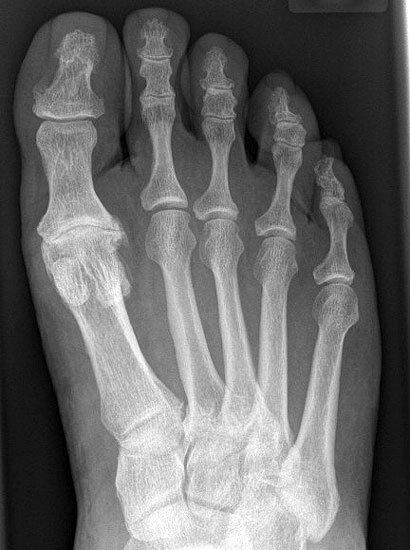

• Röntgenaufnahmen des Vorfußes (unter Belastung) im dorsoplantaren und seitlichen Strahlengang (Abb. 1a+b)

• Beurteilung des Erkankungsstadiums anhand der typischen Arthrosekriterien (Einteilung nach Regnauld) 2

• Beurteilung des Intermetatarsal-Winkels (IMA), des Hallux valgus-Winkels (HVA), mögliche Korrektur der des IMA von 6° durch alleinige Arthrodese, darüber hinaus evtl. zusätzliche MT-I-Korrektur notwendig 101112

• Beurteilung des Metatarsale-Index und der Zehenlänge DI und II, insbesondere nach Voroperationen hinsichtlich einer evtl. notwendigen Verlängerung des ersten Strahls durch Knochenspaninterposition